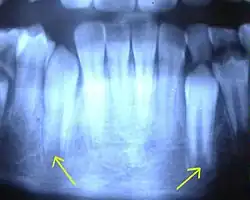

Mit Calciumhydroxid wird eine natürliche Hartsubstanzbildung an der Wurzelspitze über 6 bis 18 Monate angeregt. Calciumhydroxid stimuliert über seinen stark basischen pH-Wert reaktiv langsam die Neubildung von Zahnhartsubstanz. Nach einer röntgenologisch nachweisbarer Apexifikation kann die abschließende Wurzelkanalfüllung relativ gefahrlos hinsichtlich einer unerwünschten Überfüllung durchgeführt werden.[2]